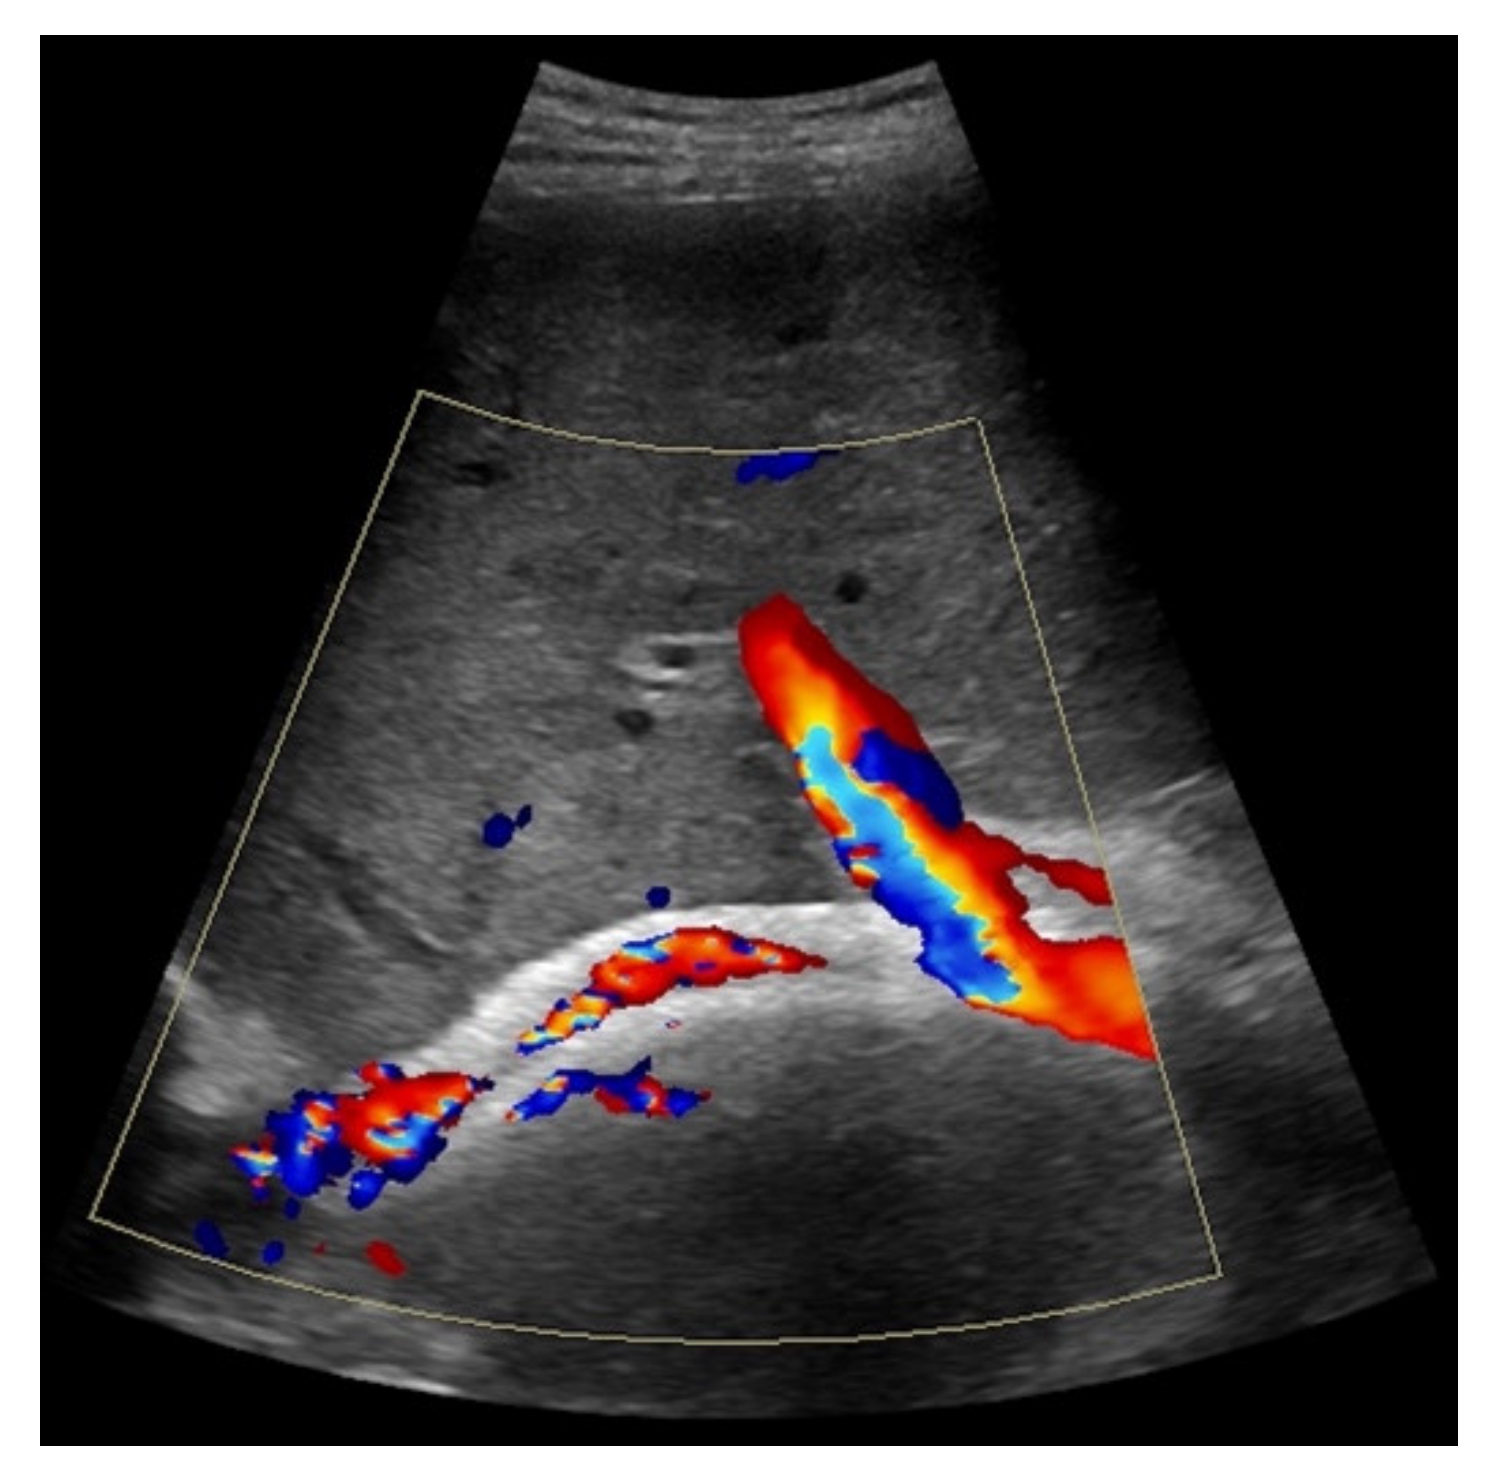

Figure 7. 52-year-old female patient with irregular presentation of the transjugular intrahepatic portosystemic shunt (TIPS) on B-mode ultrasound (a) and partial flow on Color Doppler ultrasound (CDUS) (b). After contrast administration, in contrast to CDUS, regular and continuous contrast of the TIPS is seen without evidence of thrombotic alterations or occlusion (c).

Considering findings from CDUS and CEUS examination, in eight patients results were inconsistent (7.6%). Five patients who were only partially assessed via Color Doppler ultrasound showed a regular perfusion by using CEUS (Figure 7), two patients in whom inconspicuous TIPS perfusion was registered by CDUS showed partial occluding stent thrombosis by CEUS while in one patient suspected stent thrombosis in CDUS could not be verified by CEUS (Table 3).